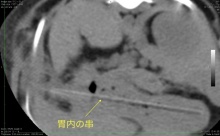

飼い主さんは非常に心配されており、積極的な検査を希望されましたので、CTを撮影することになりました。

そしてCTを撮影してみると・・・見事に胃の中いっぱいにある串が映し出されました。また、その串の一部は胃を貫通して、数センチ胃の外に出ていることもわかります。こういう状態であれば内視鏡で取るのは難しくなりますので、開腹手術で串を取り出しました。

串はCTで写ったとおり、胃から数センチ飛び出していました。幸い肝臓や脾臓に刺さってはいませんでしたので、大事にならずにすみました。

このようにCTもレントゲンを同じX線ですが、CTはレントゲンに比べて、格段に多くの情報を得ることが出来ます。そのため、お腹のなかの腫瘍であれば、どこから由来の腫瘍かということや、周囲の臓器の癒着具合など、またレントゲンには写らない肺転移などもCTなら発見する確率は格段に上がります。